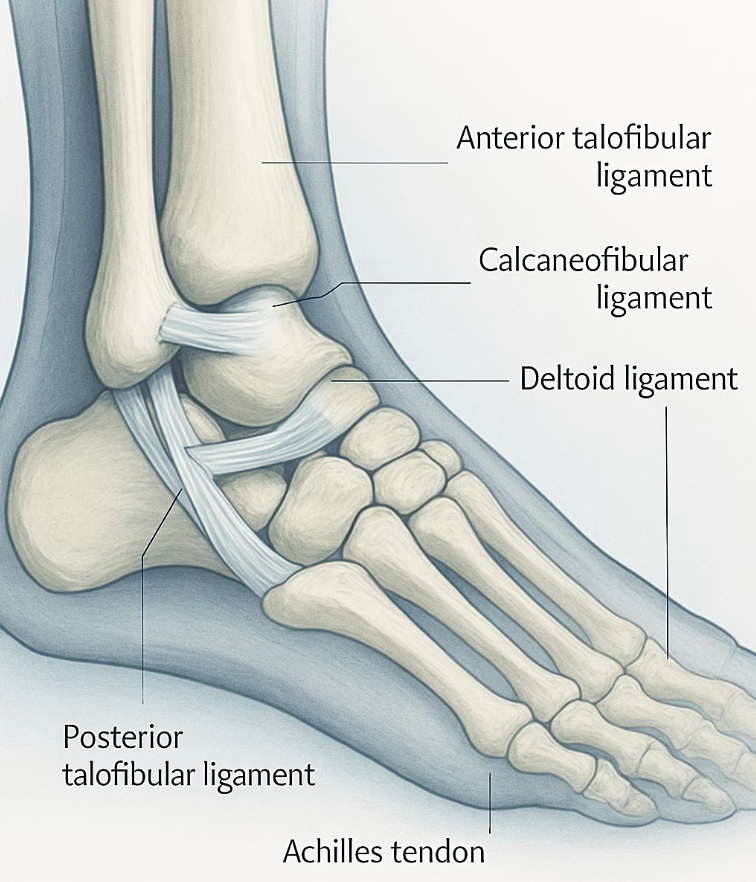

복숭아뼈 주변의 통증을 호소하는 분들의 가장 흔한 원인은 바로 발목을 지지하는 인대나 힘줄에 미세한 손상이 쌓여 염증이 생긴 경우입니다. 우리 발목의 인대와 힘줄은 관절을 안정적으로 잡아주는 ‘튼튼한 밧줄’과 같습니다. 하지만 과도한 운동, 불편한 신발 착용, 혹은 과거에 접질렸던 부상 등으로 인해 이 밧줄이 약해지거나 계속해서 무리한 자극을 받으면, 결국 닳고 찢어지며 통증을 유발하는 것이죠.

“예전에 발목을 심하게 삔 적이 있어요”라고 말하는 분들이 많습니다. 바로 이것이 현재 통증의 뿌리일 가능성이 매우 높습니다. 한번 늘어난 인대는 원래의 짱짱함을 완전히 되찾기 어렵습니다. 이렇게 인대가 느슨해진 상태를 ‘만성 발목 불안정증’이라고 하는데, 이 경우 걸을 때마다 발목 관절이 미세하게 흔들리면서 주변 힘줄과 연골에 계속해서 스트레스를 주게 됩니다.